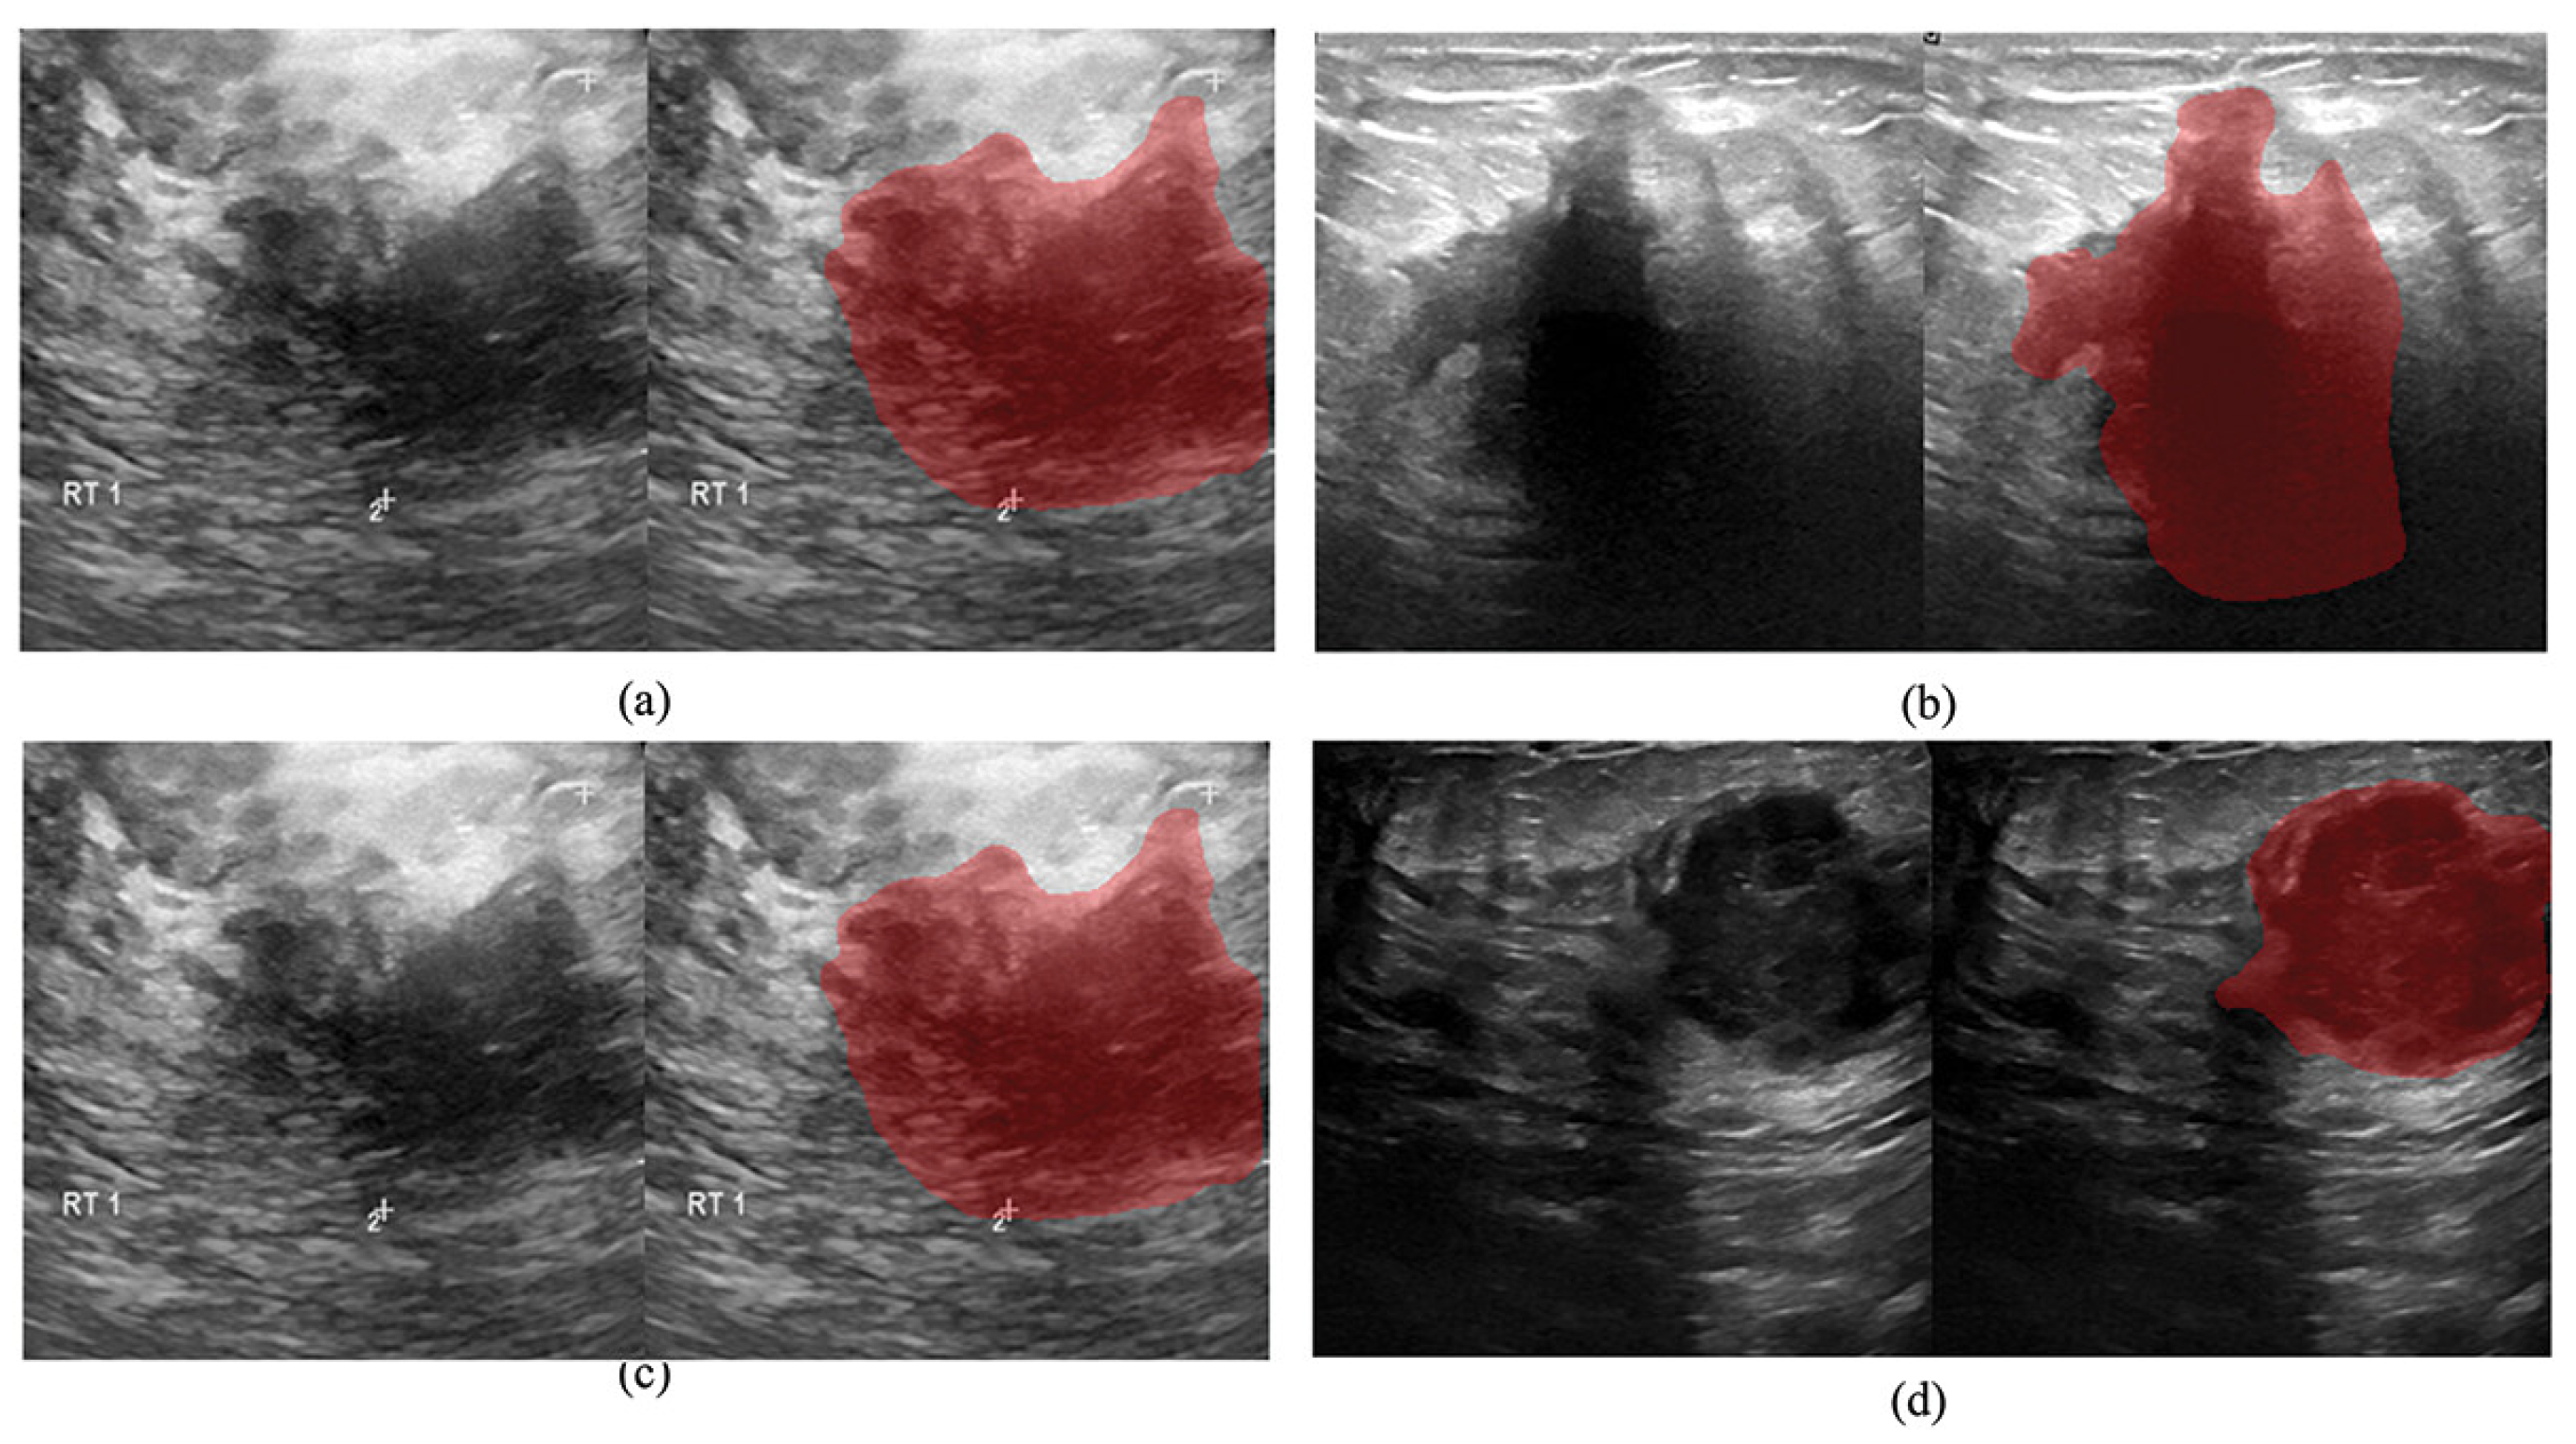

- Xian, M.; Zhang, Y.; Cheng, H.; Xu, F.; Zhang, B.; Ding, J. Automatic Breast Ultrasound Image Segmentation: A Survey. arXiv 2017, arXiv:1704.01472. [Google Scholar] [CrossRef]

- Deepak, G.D.; Bhat, S.K. A comparative study of breast tumour detection using a semantic segmentation network coupled with different pretrained CNNs. Comput. Methods Biomech. Biomed. Eng. Imaging Vis. 2024, 12, 2373996. [Google Scholar] [CrossRef]